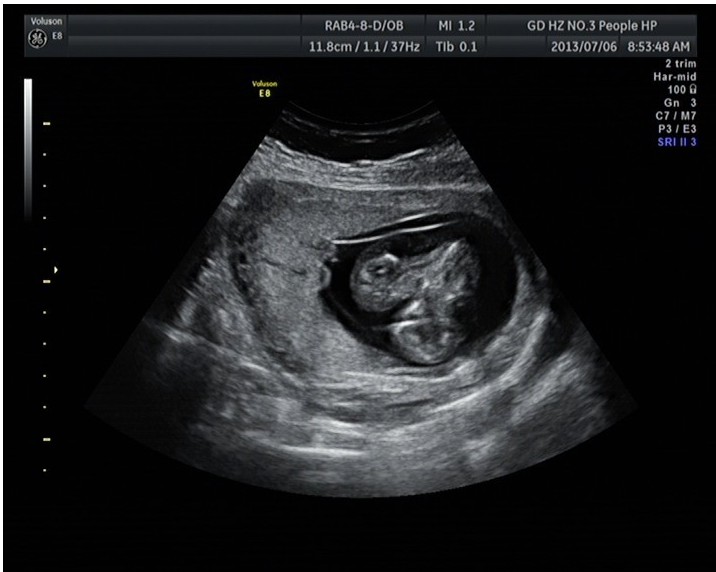

隨著環(huán)境污染日益嚴重,隨著各種地溝油的誕生,隨著各樣鎘大米的泛濫……我們的健康越來越受到威脅,很多疾病也隨之接踵而至,胎兒先天性疾病也越來越多見。7月6日,我院超聲科王瑤醫(yī)生在做胎兒產(chǎn)前NT篩查中發(fā)現(xiàn)一例孕約11周+的聯(lián)體雙胎。超聲所見:增大的子宮內(nèi)可見聯(lián)體雙胎兒回聲,可見兩個胎頭不能分離,胸部及腹部融合,可見一個增大的心臟。

聯(lián)體嬰兒B超圖像